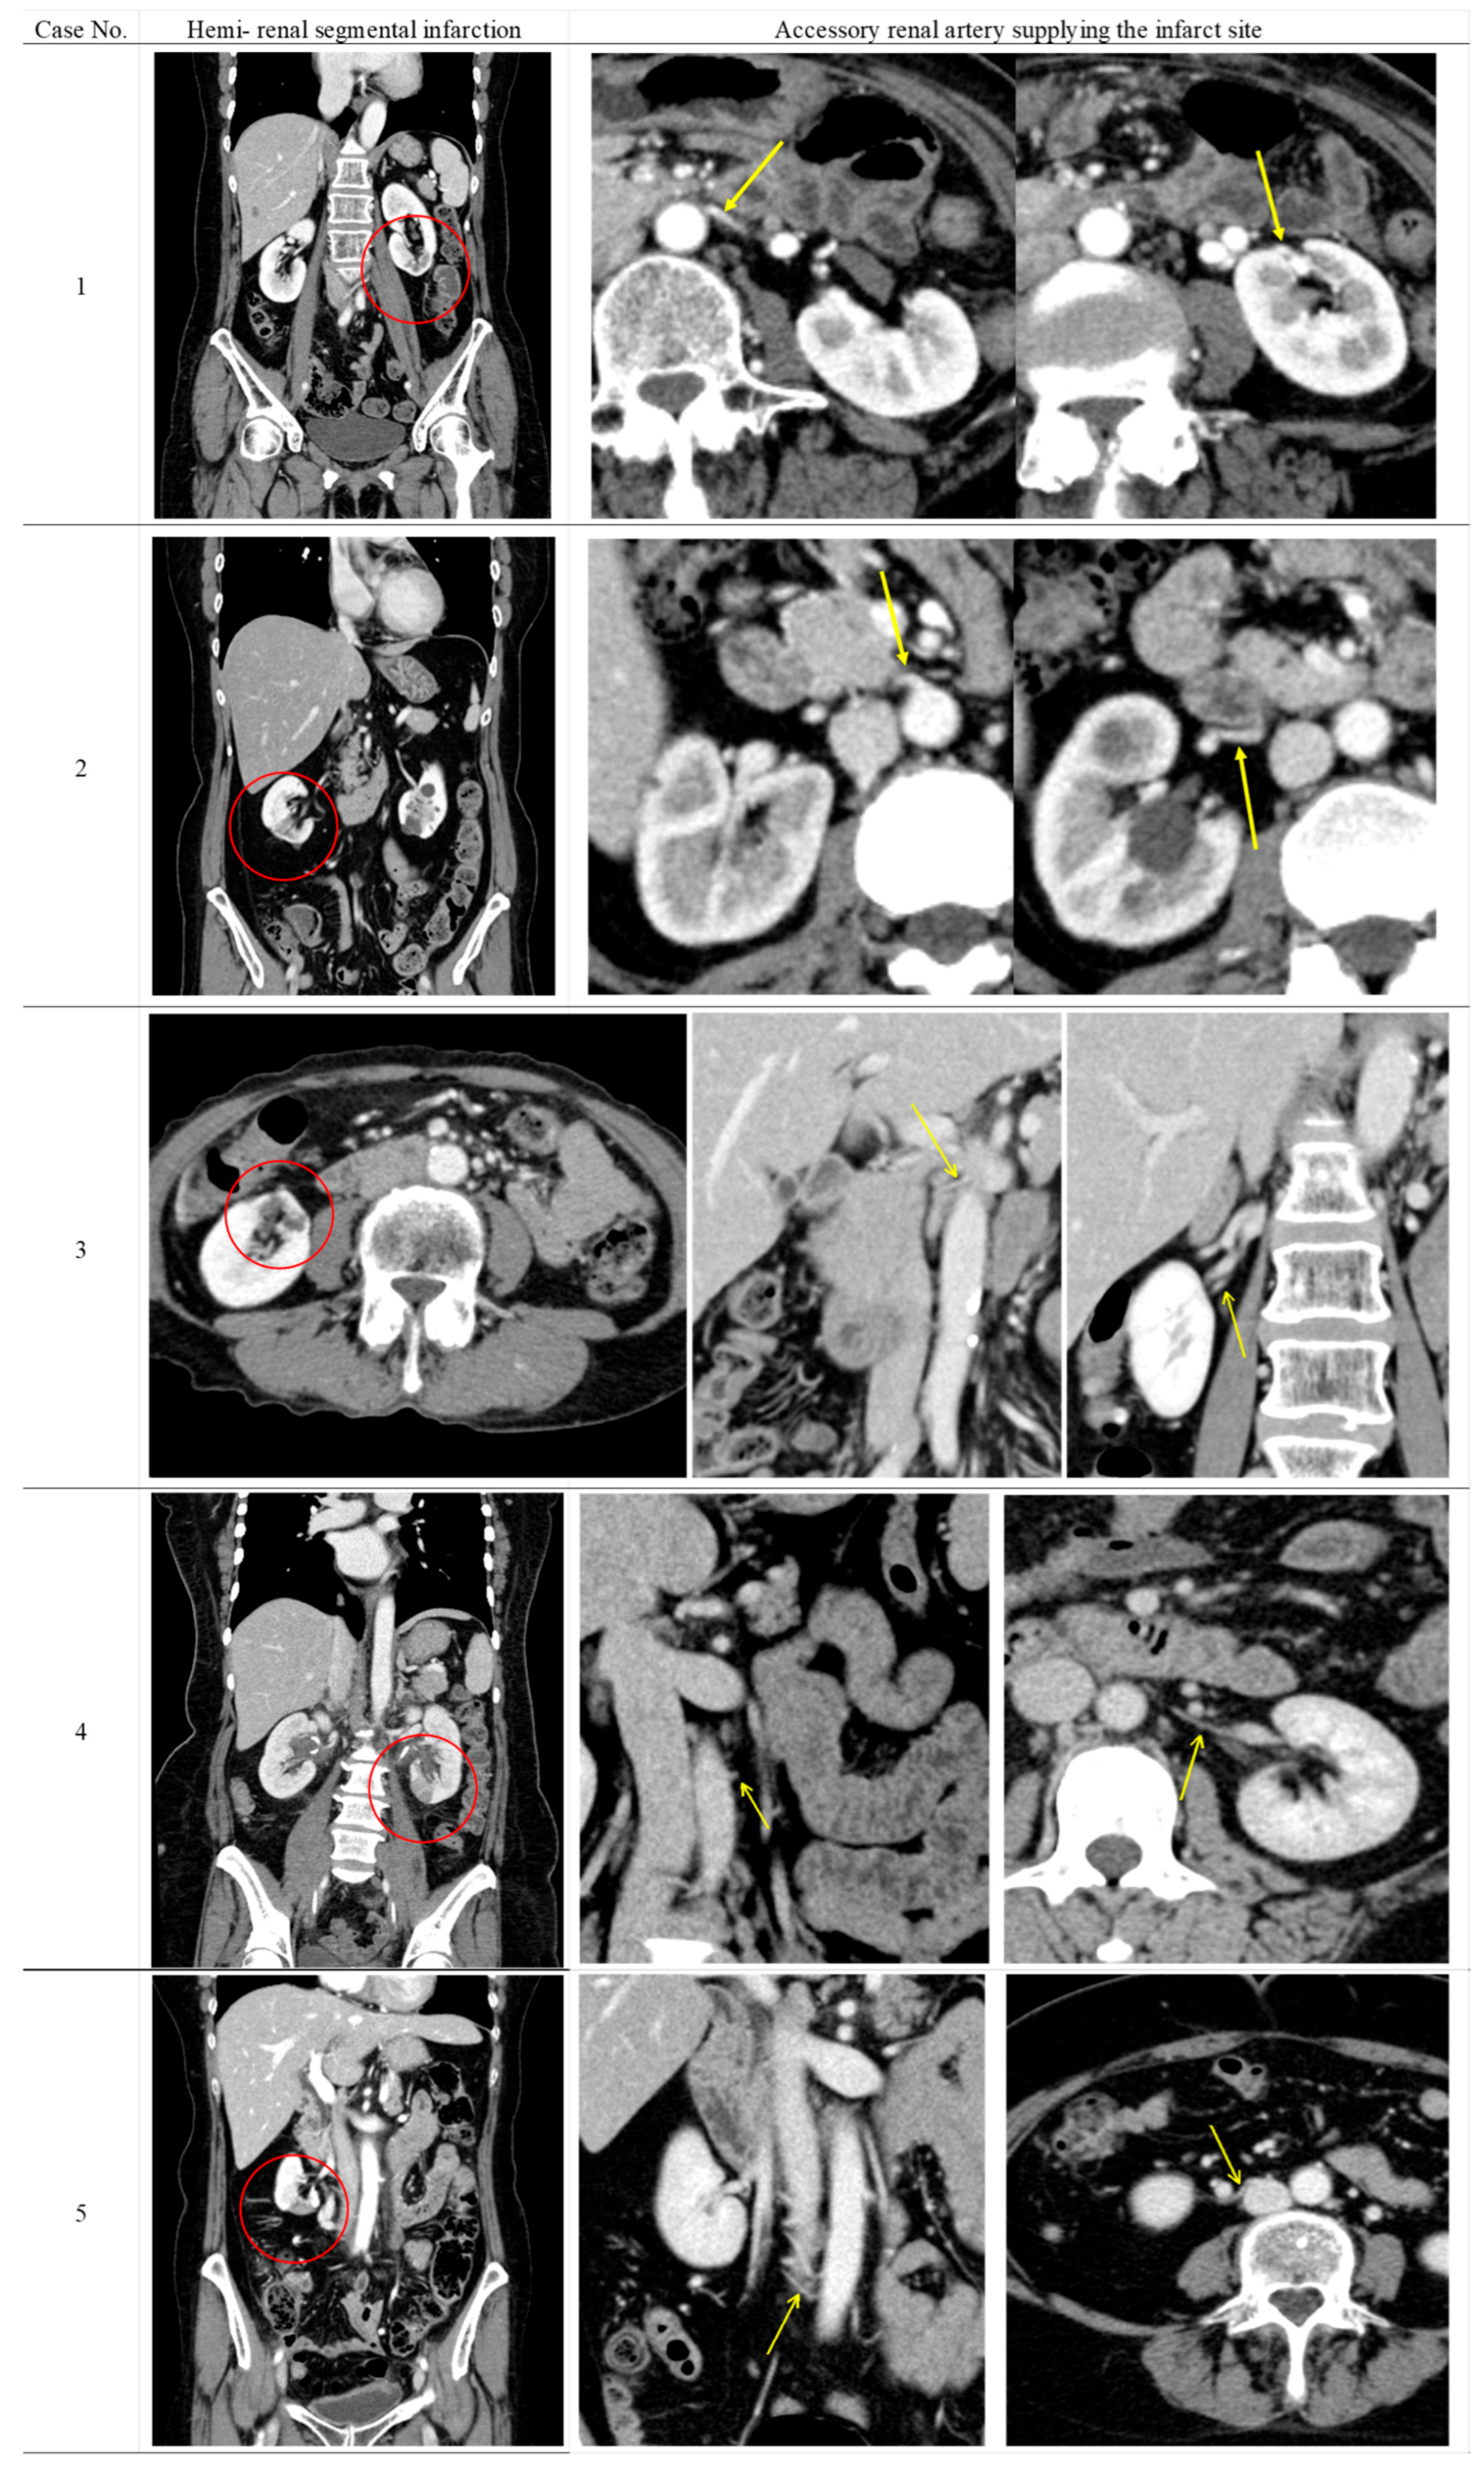

Table 2 shows the radiological findings and perioperative serum creatinine levels of patients who developed renal perfusion defects following surgery. Furthermore, the CECT findings of five patients with suspected renal perfusion defects due to ARA obstruction are shown in Figure 2. None of the six patients had clinical or laboratory findings of urinary tract infection at the time of CEST when perfusion defects were detected. Renal parenchymal fibrosis, cortical atrophy, and parenchymal thinning were observed as universal findings in all patients showing renal contrast defects.

In five of the six cases, ARAs supplying the infarcted renal segments were identified on preoperative CECT, and arterial obstruction was confirmed on postoperative imaging. Three of the five patients had an infarction in the lower pole of the kidney. These findings indicated that surgical intervention was the cause of segmental renal infarction. The remaining case was considered latent pyelonephritis due to the absence of identifiable collateral circulation and minimal parenchymal changes.

Figure 2. Contrast-enhanced computed tomography findings in five patients with renal perfusion defect potentially involving accessory renal artery obstruction.